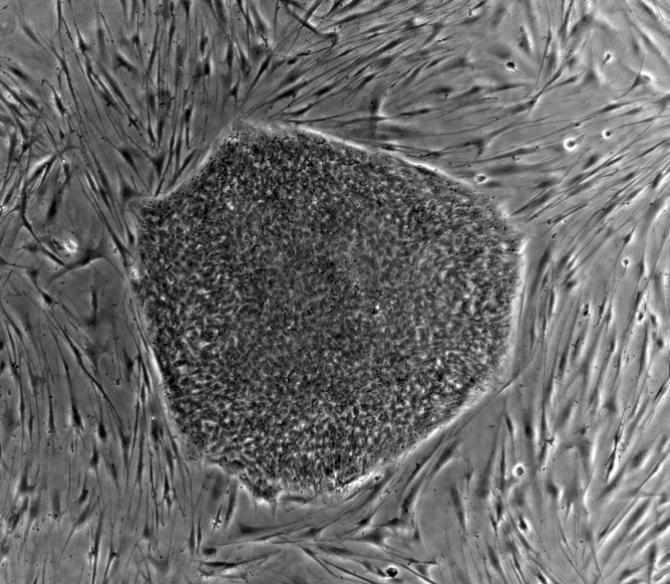

人類(lèi)胚胎干細胞(hES)

干細胞一般有兩種來(lái)源,一種少部分存在于成年個(gè)體的組織器官中,例如:我們如果去少量獻血,并不會(huì )馬上死掉,骨髓中的造血干細胞會(huì )馬上動(dòng)員起來(lái),分化為血液細胞,這樣你又可以活蹦亂跳了。而另外一種,功能更為強大,從發(fā)育早期胚胎分離得到的胚胎干細胞,它與成體干細胞不同,具有更高的多能性,可以轉變?yōu)槿梭w的任何的細胞、組織甚至器官,是一種真正萬(wàn)能細胞。